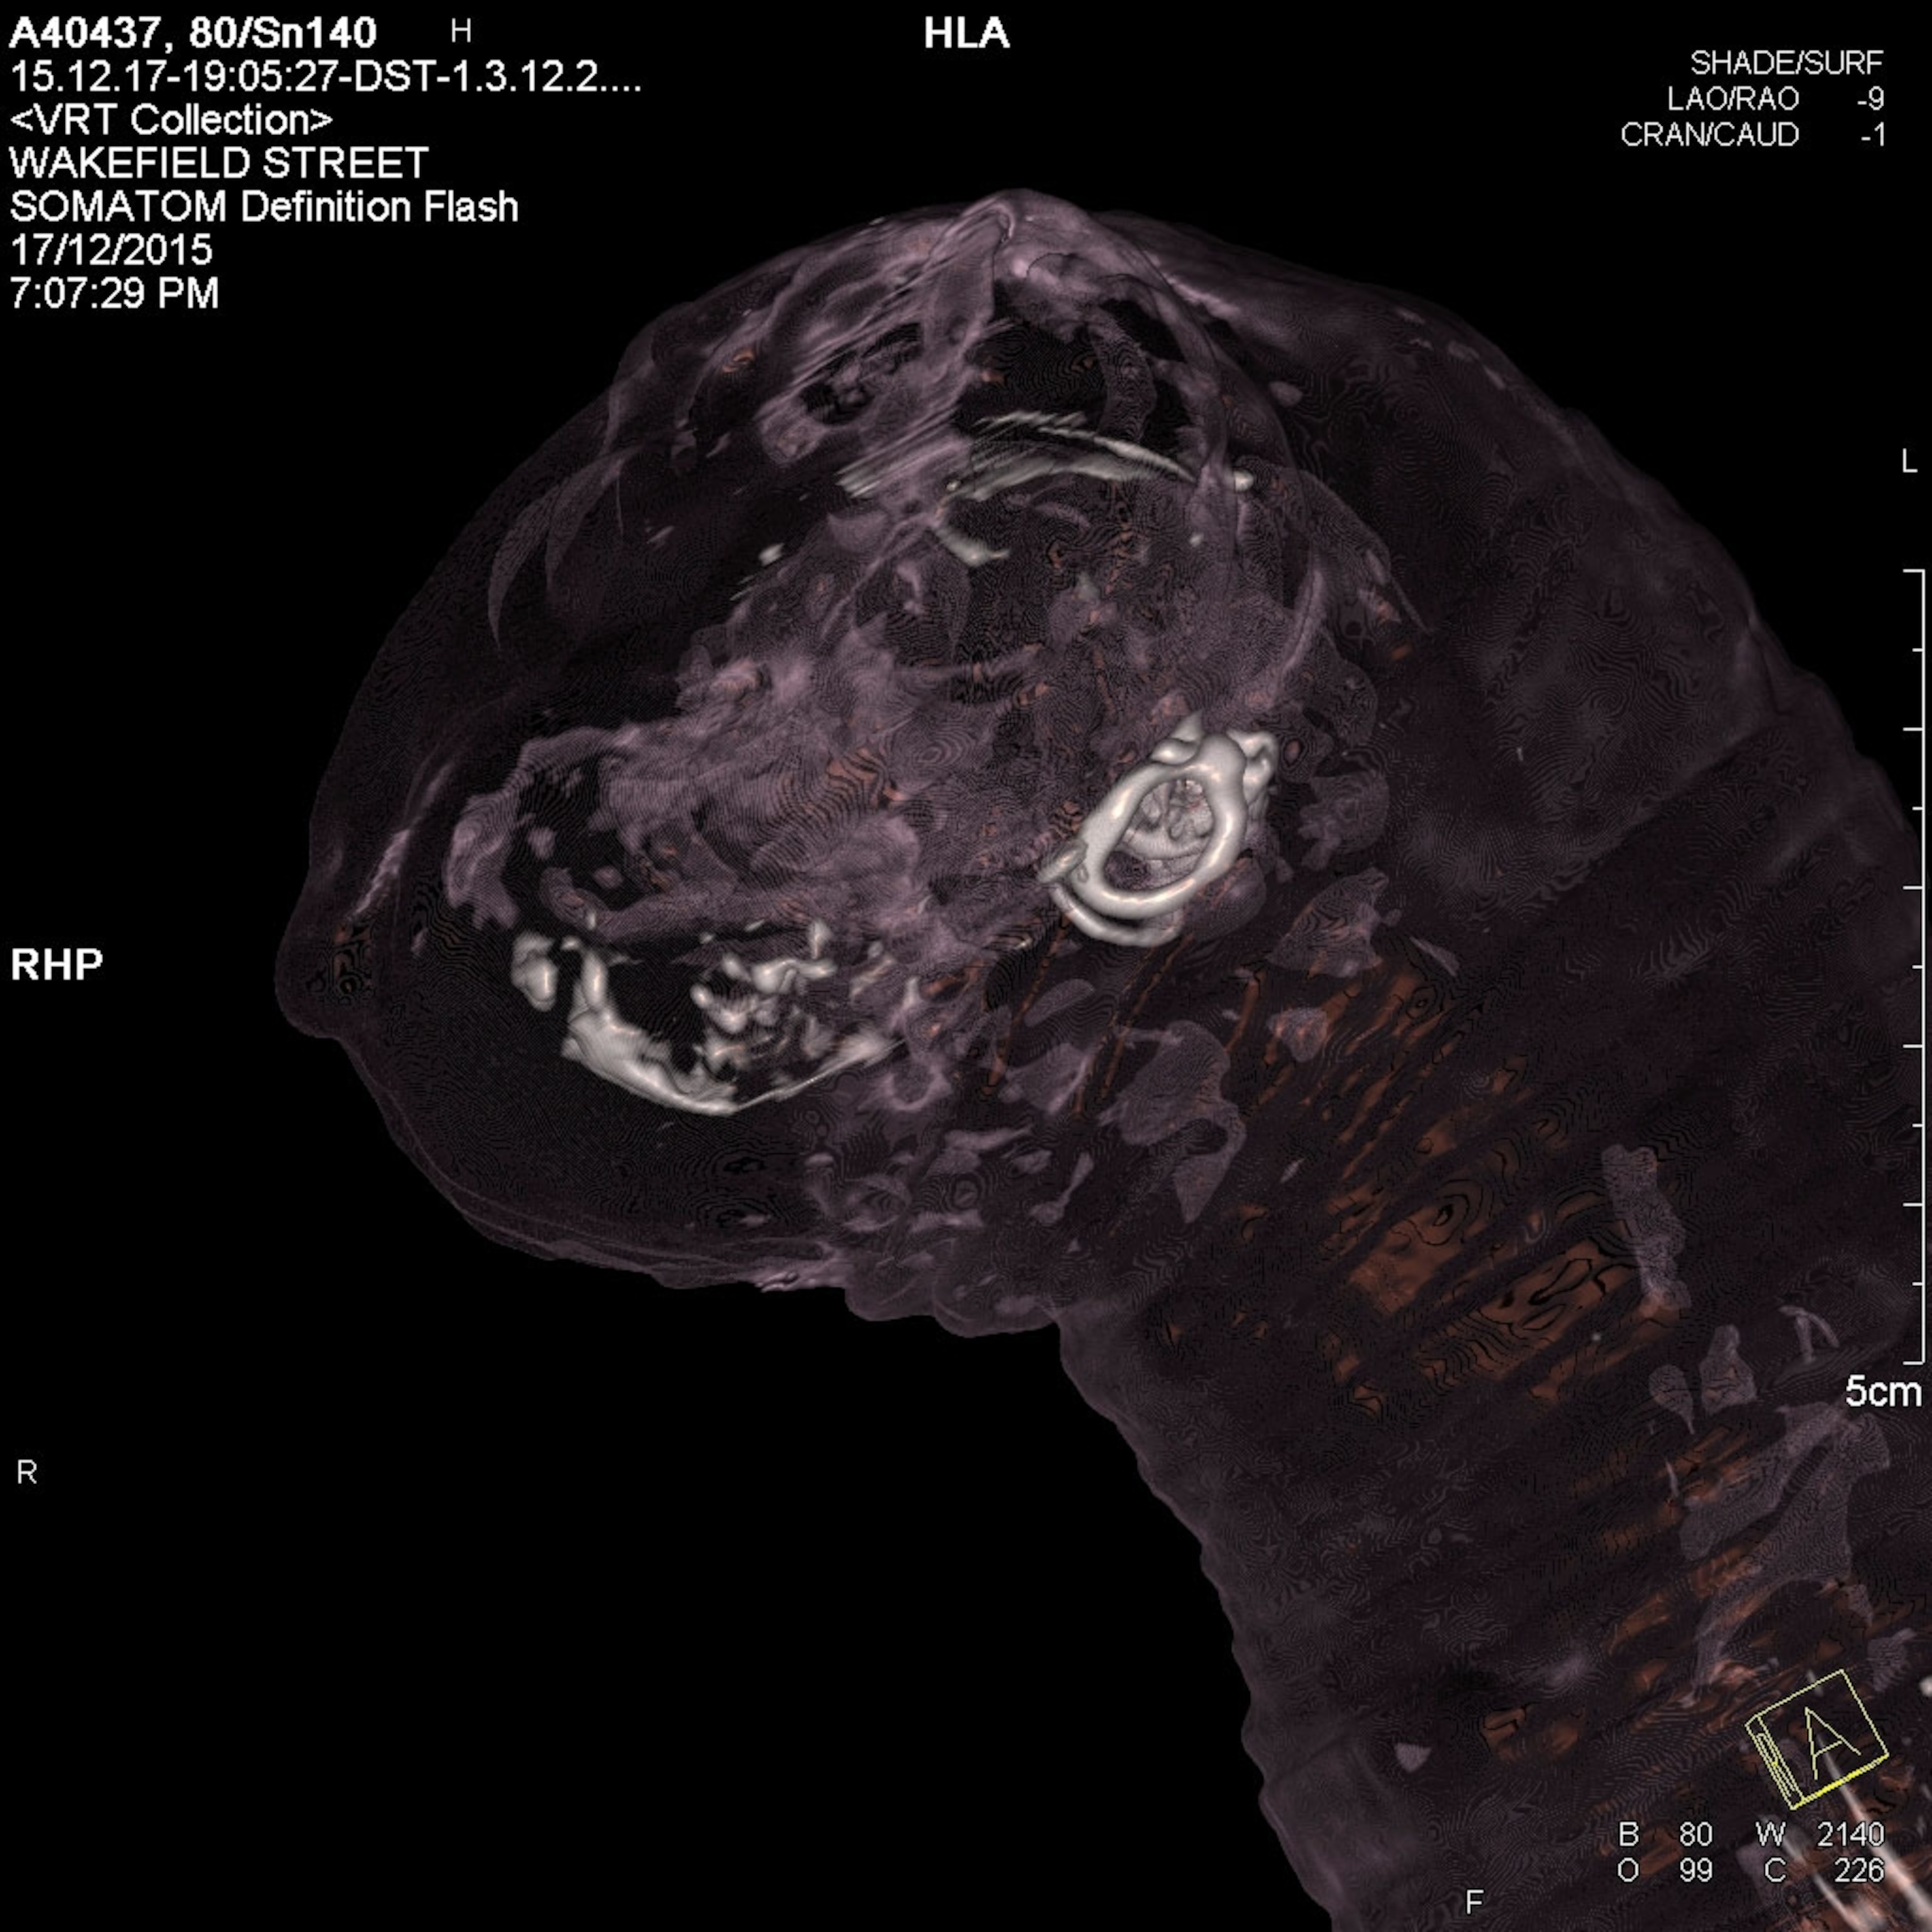

The new kind of CT scan has been successfully tested on cat mummies from the collections of the South Australian Museum. While the exact ages of these mummies are unknown, feline mummies were fairly common in Egypt from about 600 B.C. until A.D. 250.

The new technique, known as atomic number imaging, instead uses two kinds of x-rays to peer inside stuff and figure out the hidden composition based on a material’s atomic number—one of the defining characteristics of a chemical element. For instance, the scans can distinguish between bones filled with calcium and phosphorous and muscle, which is mostly carbon.

Bewes and Craig's scans show that these two cats did have broken necks. But the scans also teased out nearby fractures in the dried tissue, which mean the breaks likely happened after mummification, ruling out at least one possible cause of death for these animals.